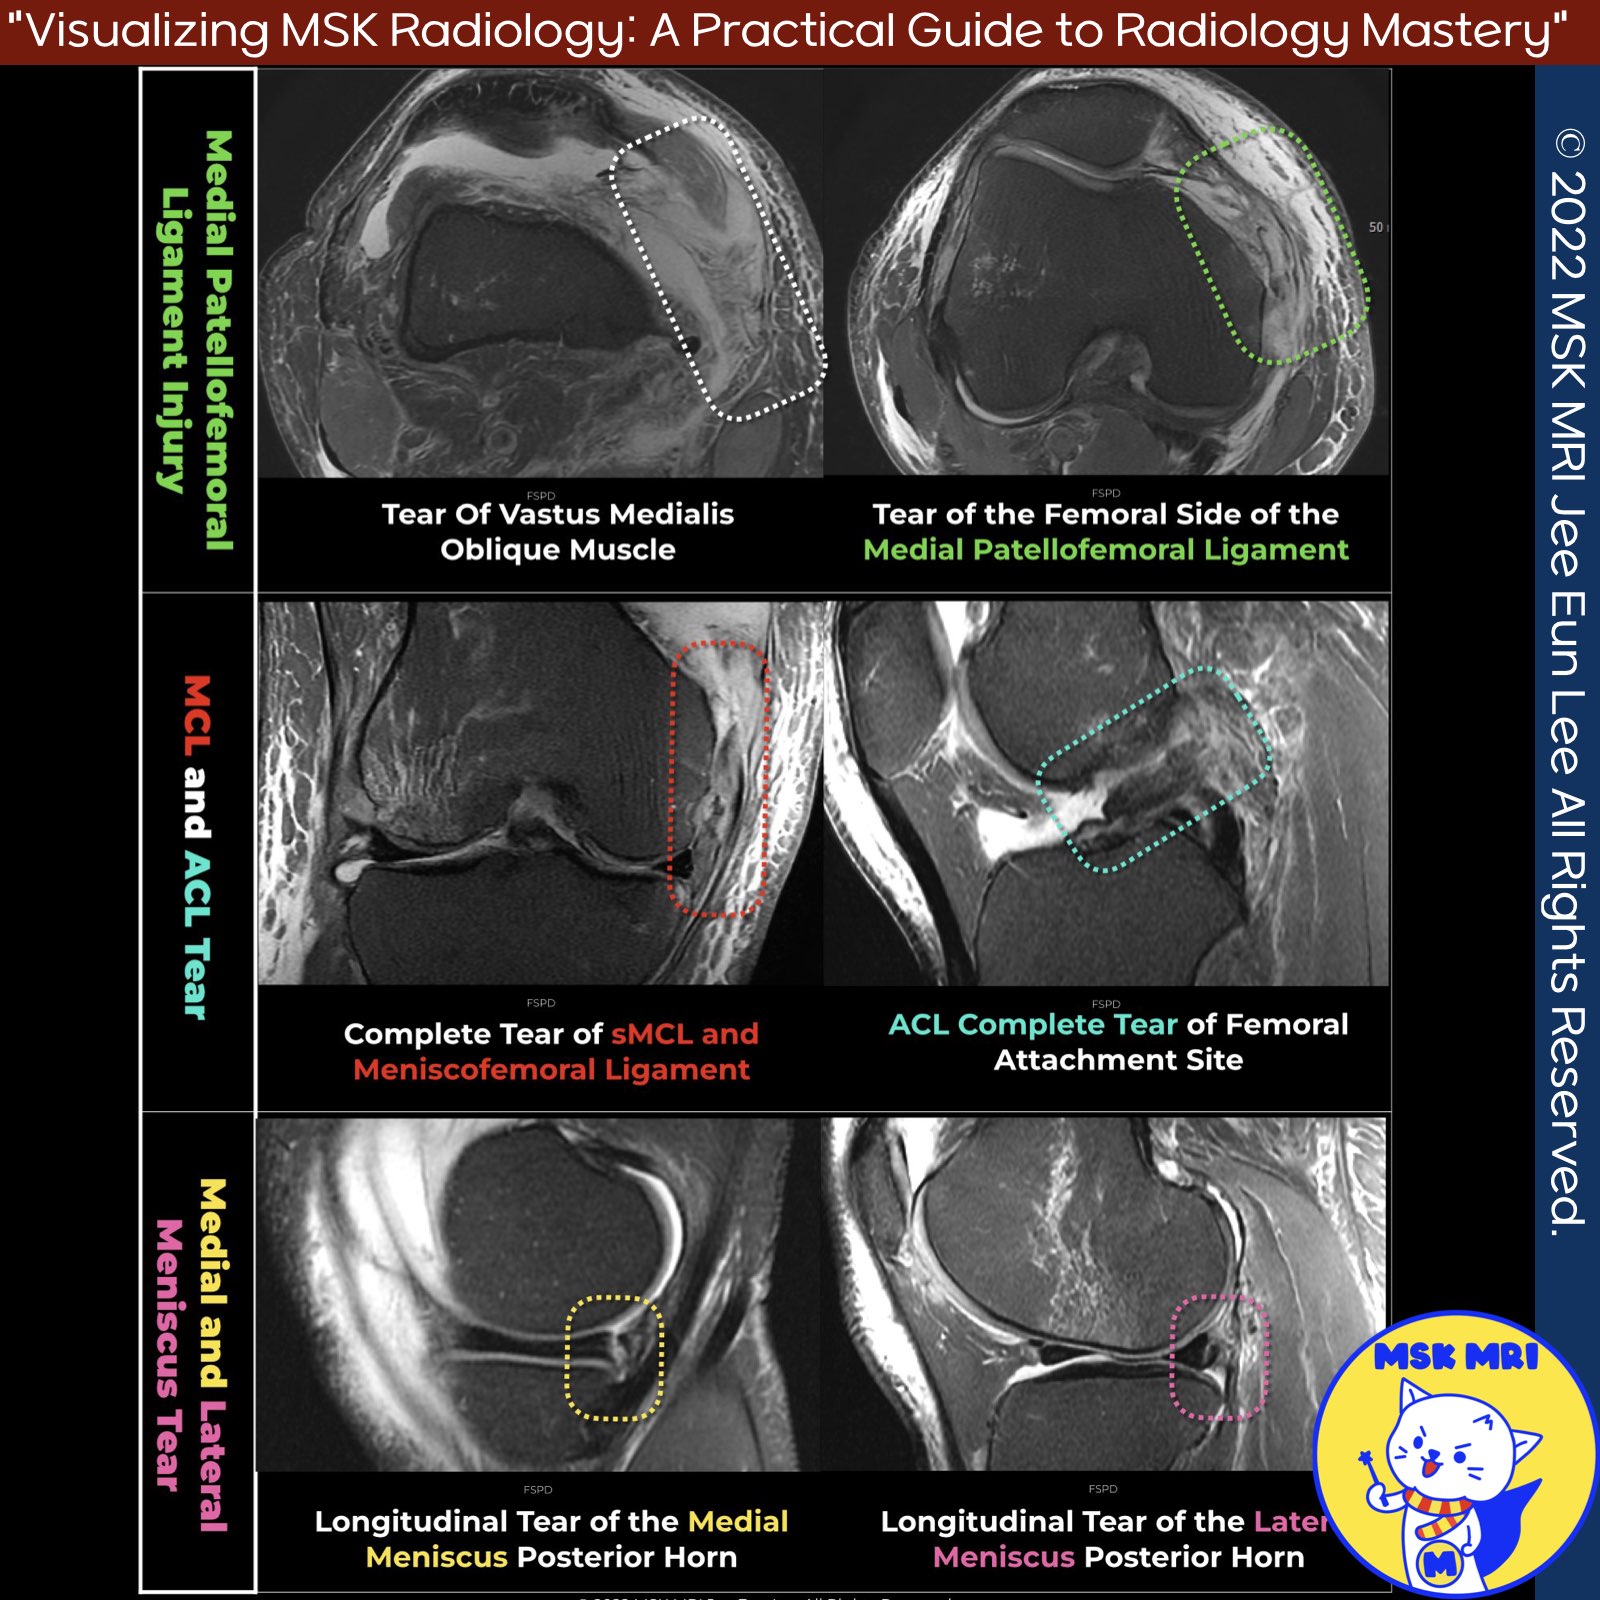

📌O'Donoghue's Unhappy Triad

- The O'Donoghue unhappy triad refers to a combined injury involving three specific structures: the anterior cruciate ligament (ACL), the medial collateral ligament (MCL), and the medial meniscus.

📌Expansion to Tetrad and Pentad Lesions

- Tetrad Lesion: When there is an additional injury to the Medial Patellofemoral Ligament (MPFL), the condition escalates to what is termed a tetrad lesion.

- Pentad Lesion: Further complexity is added with a pentad lesion, which includes the injuries of a tetrad lesion plus an additional injury to the lateral meniscus or popliteomeniscal fascicles.